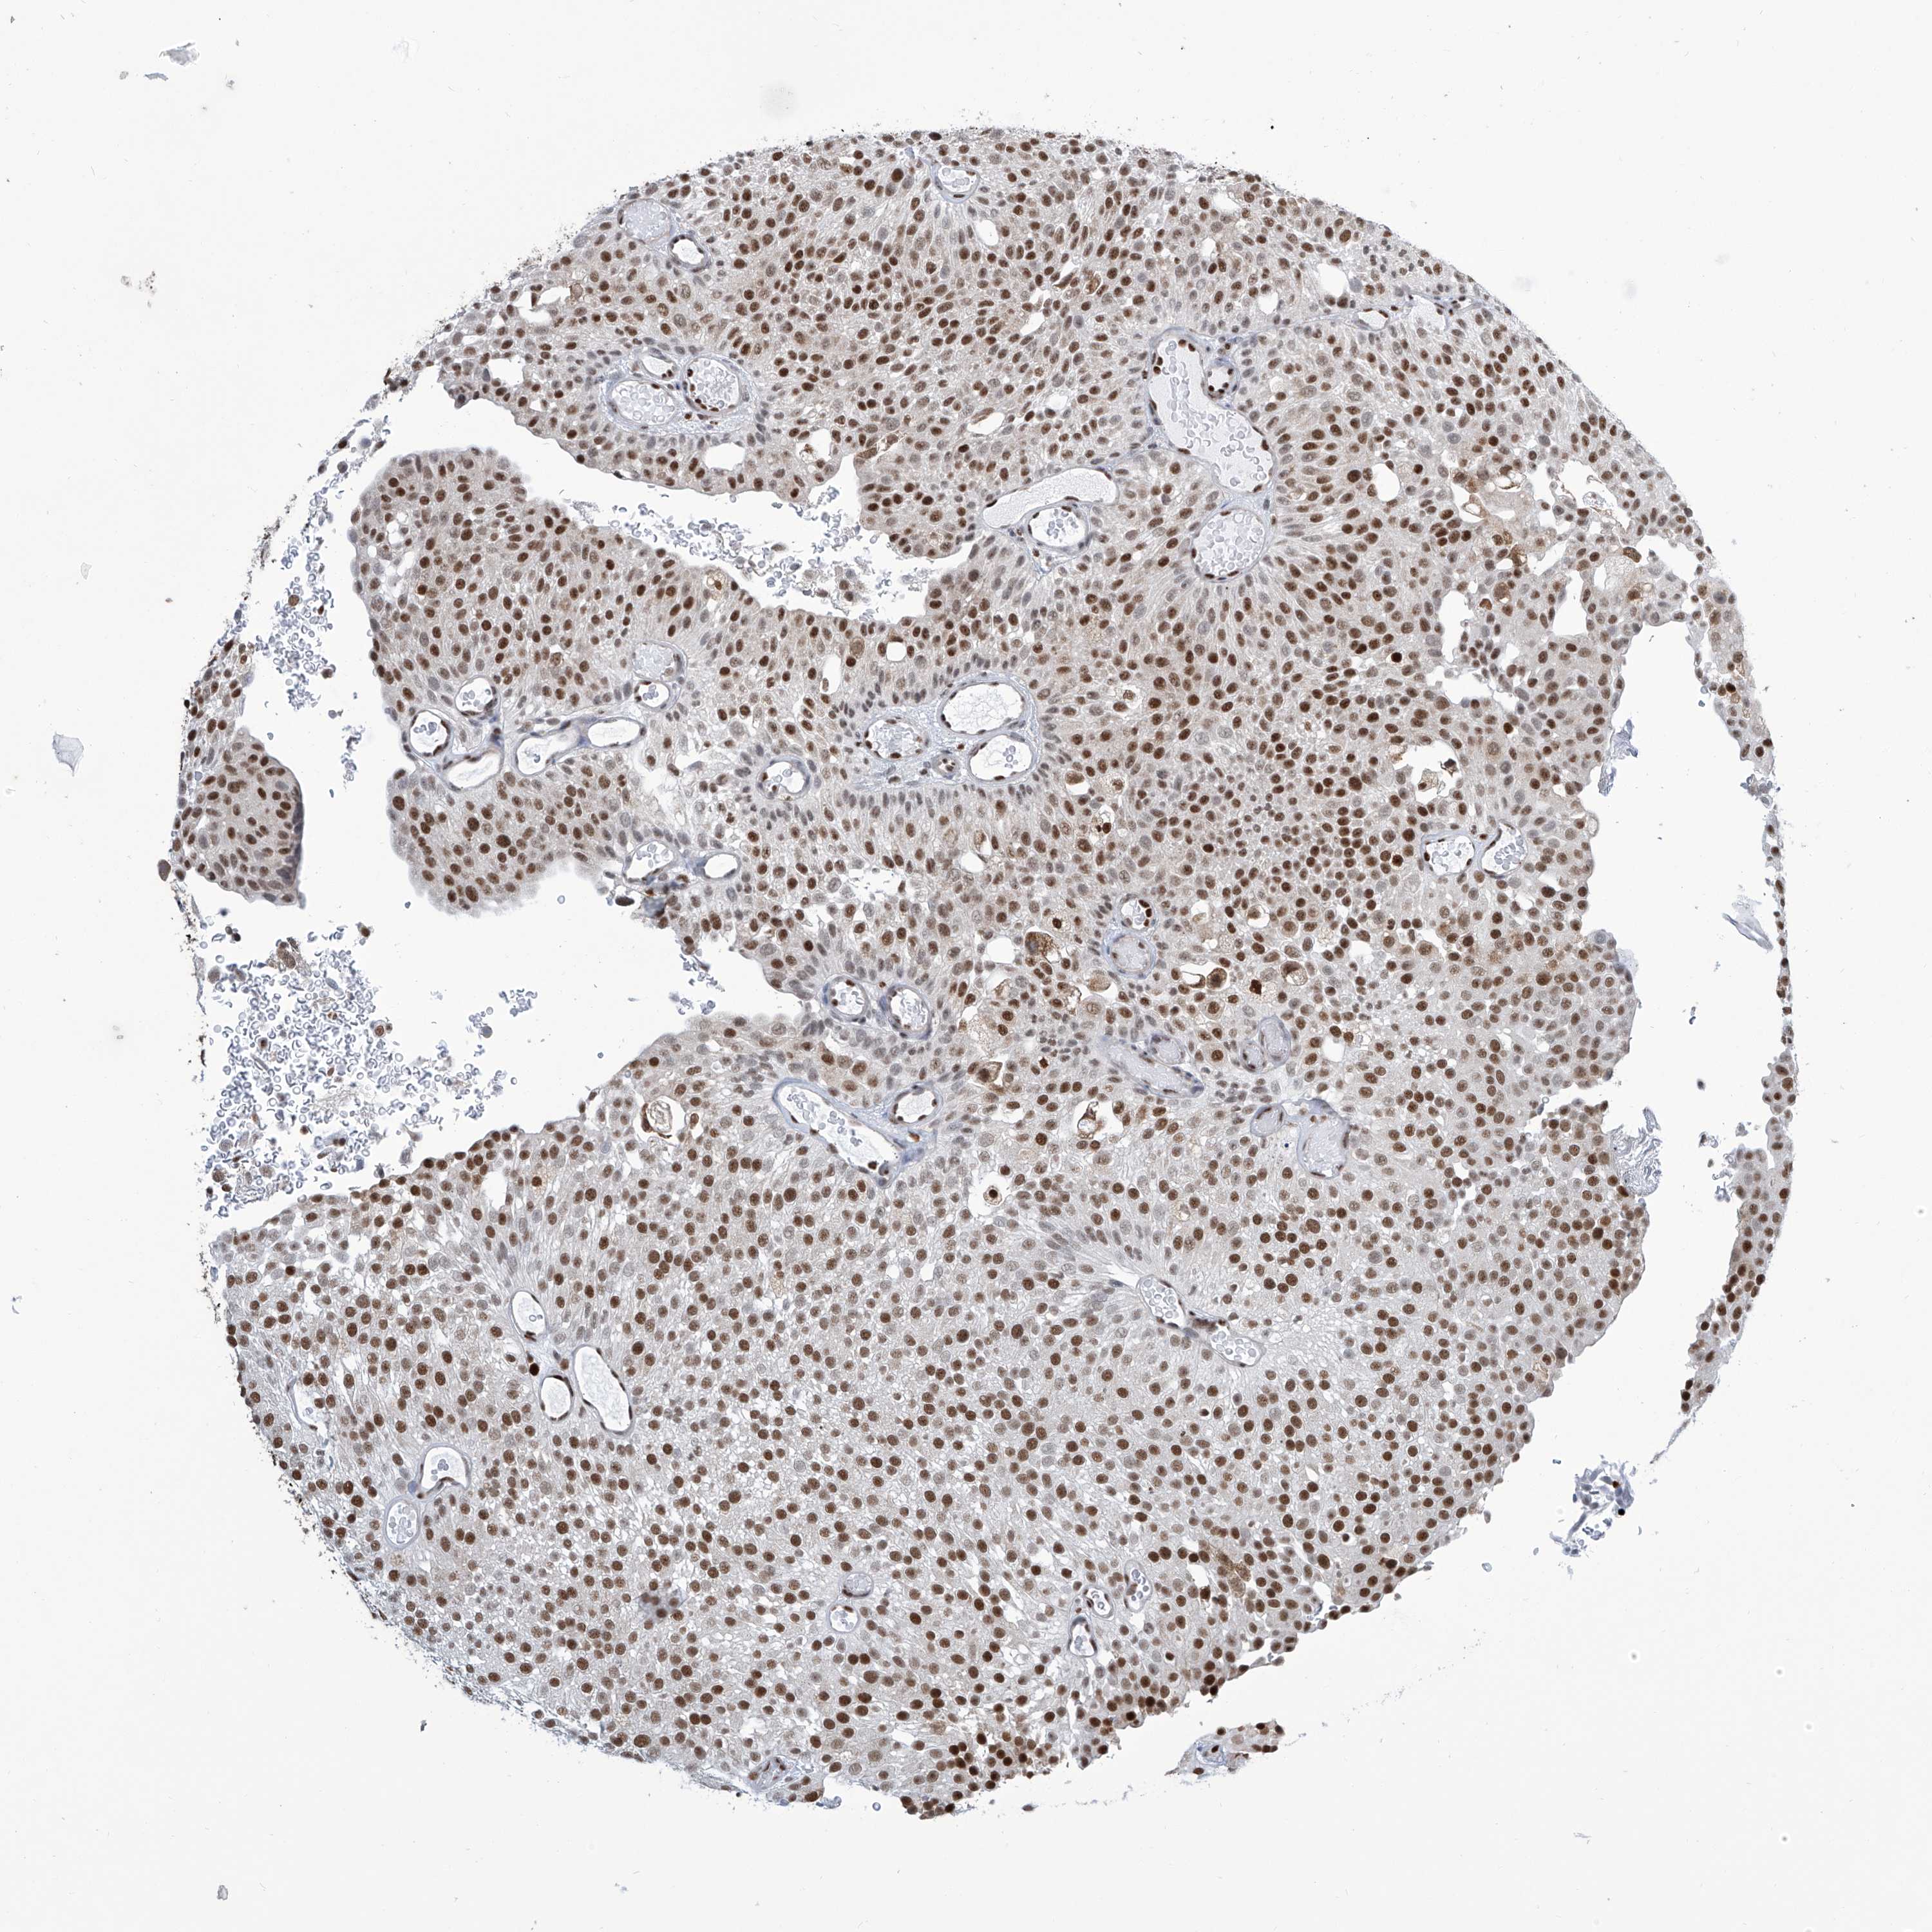

UROTHELIAL CANCER - Protein expressioni

A mouse-over function shows sample information and annotation data. Click on an image to view it in a full screen mode. Samples can be filtered based on level of antibody staining by selecting one or several of the following categories: high, medium, low and not detected. The assay and annotation is described here.

Note that samples used for immunohistochemistry by the Human Protein Atlas do not correspond to samples in the TCGA dataset.

Antibody stainingi

Antibody staining in the annotated cell types in the current human tissue is reported as not detected, low, medium, or high, based on conventional immunohistochemistry profiling in selected tissues. This score is based on the combination of the staining intensity and fraction of stained cells.

Each image is clickable and will lead to virtual microscopy that enables deeper exploration of all samples and also displays staining intensity scores, fraction scores and subcellular localization as well as patient and tissue information for each sample.

Antibody HPA031962

Staining

High

Medium

Low

Not detected

Intensity

Strong

Moderate

Weak

Negative

Quantity

>75%

75%-25%

<25%

None

Location

Nuclear

Cytoplasmic/membranous

Cytoplasmic/membranous,nuclear

Urothelial carcinoma, Low grade

Urothelial carcinoma, High grade